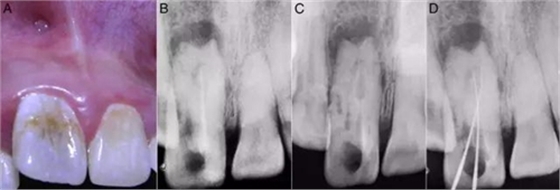

檢查:11曾做過根管治療、叩診(+)。冠修復脫落,暴露根管口和齲壞的牙體組織,還有近遠中腭溝深齲延伸至釉牙骨質(zhì)界。11較21尺寸要大并向唇側(cè)傾斜、冠1/3突出,中間部分凹陷。唇前庭有局部的棕色斑點和竇道開口(圖1A)。牙髓電活力測試和冷熱診均呈陰性反應。

X線檢查:11暗示有牙內(nèi)陷的發(fā)育畸形,冠根呈桶狀。根管復雜但只有一個根尖孔,先前的根管充填并不徹底。還有中等大小的根尖周病變(圖1B)。

圖1:A:11外部形態(tài);B:11之前的根管治療;C:牙膠去除后,牙內(nèi)陷的形狀、可以看出復雜根管和盲袋;D:DM傾斜走形和MI在根尖區(qū)重疊。